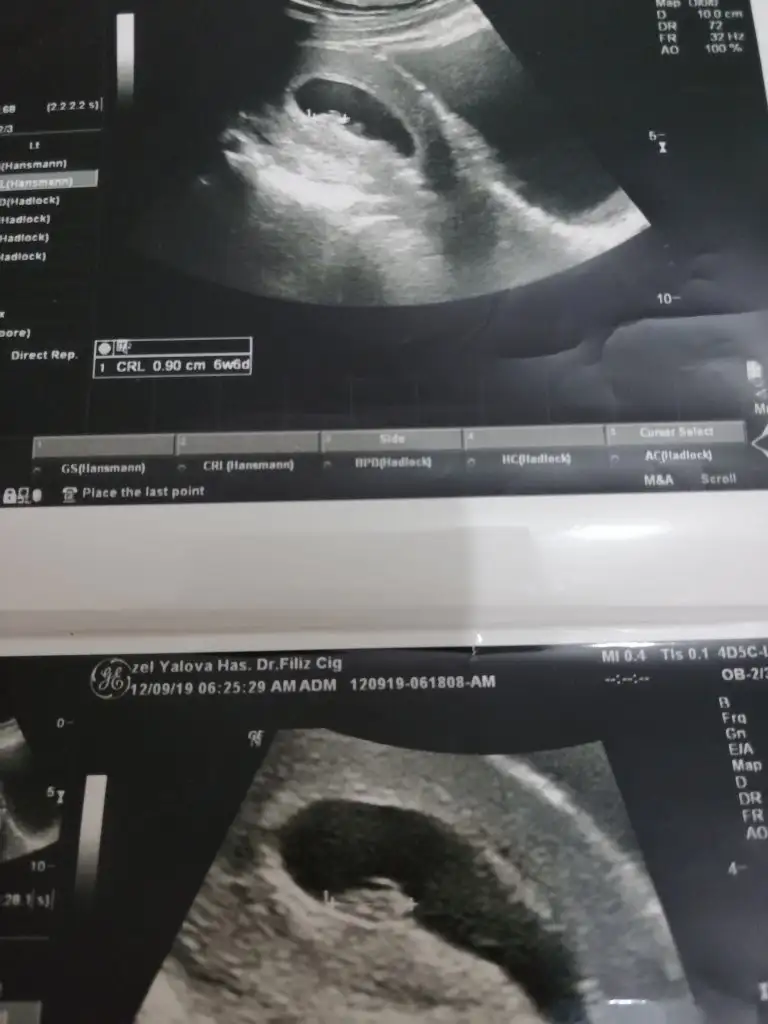

MerhabaIkra meyra ben de merak ediyorum 10haftalık görüntüsü bu acaba bakabilir misiniz?

Başka usg varmı cnm net değil